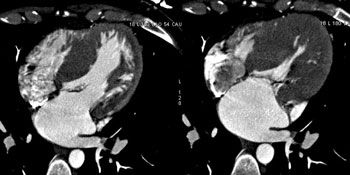

They are a major cause of progressive heart failure and death, but cardiomyopathies can be tough to spot for clinicians, and missed cases can have fatal consequences. During an ECR special focus session on Friday afternoon, expert speakers reviewed the use of imaging for diagnosing the mysterious condition and for mastering its many faces.